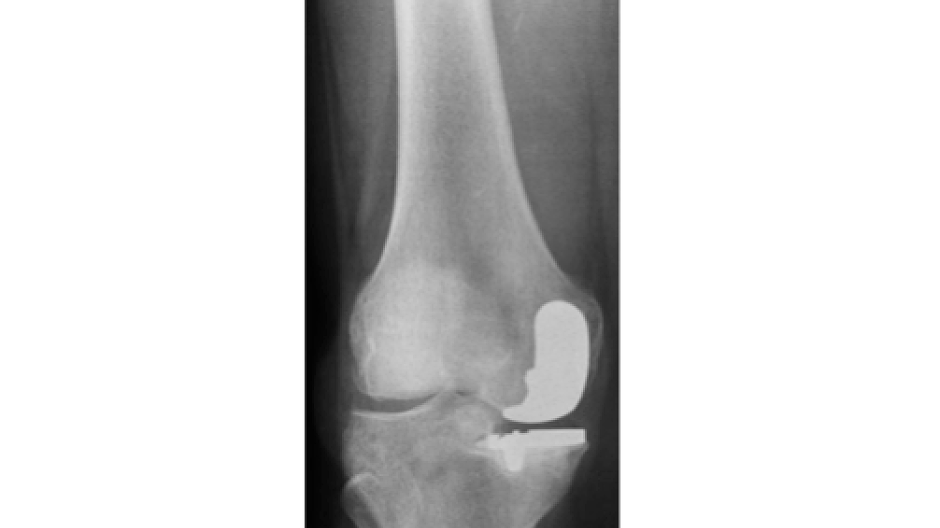

Fotos Unfallchirurgie und Orthopädie